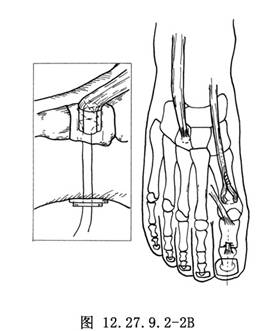

做“L”形切口顯露𧿹趾趾間關節(圖1a),將皮膚和皮下組織瓣向內、向近側拉開,找到𧿹長伸肌腱。在趾間關節近側1cm處橫斷肌腱,去除趾間關節面軟骨,用一根直徑爲0.2cm的斯氏釘或兩根直徑爲0.16cm的克氏針逆行固定,於皮下剪斷內固定針。另做一個2.5cm長的足背內側切口顯露第1蹠骨頸(圖12.27.9.2-1A),注意保護𧿹短伸肌腱,並沿切口全長切開其腱鞘。在第1蹠骨頸部位由蹠內側到外側橫向鑽孔,將肌腱經孔穿過,調整合適張力後與自身做間斷縫合(圖12.27.9.2-1B)。